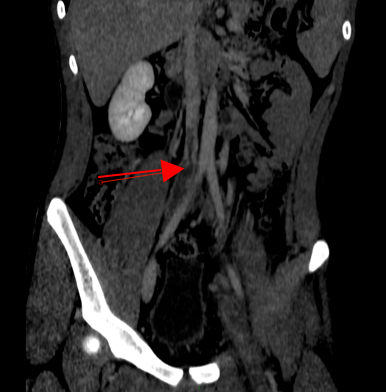

Per la storia di dolore inguino-scrotale e la difficoltà a deambulare viene eseguita una ecografia scrotale con riscontro collaterale di trombosi completa dell’asse popliteo iliaco femorale di sinistra! Per valutare l’estensione della trombosi viene eseguita angio-TC toraco-addominale che evidenzia la presenza di una parziale trombosi del tratto sottorenale della vena cava inferiore con trombosi completa di entrambe le vene iliache comuni, della vena iliaca esterna di sinistra e della femorale comune omolaterale associata inoltre a trombosi parziale della vena iliaca interna di destra (Figure 4 e 5).